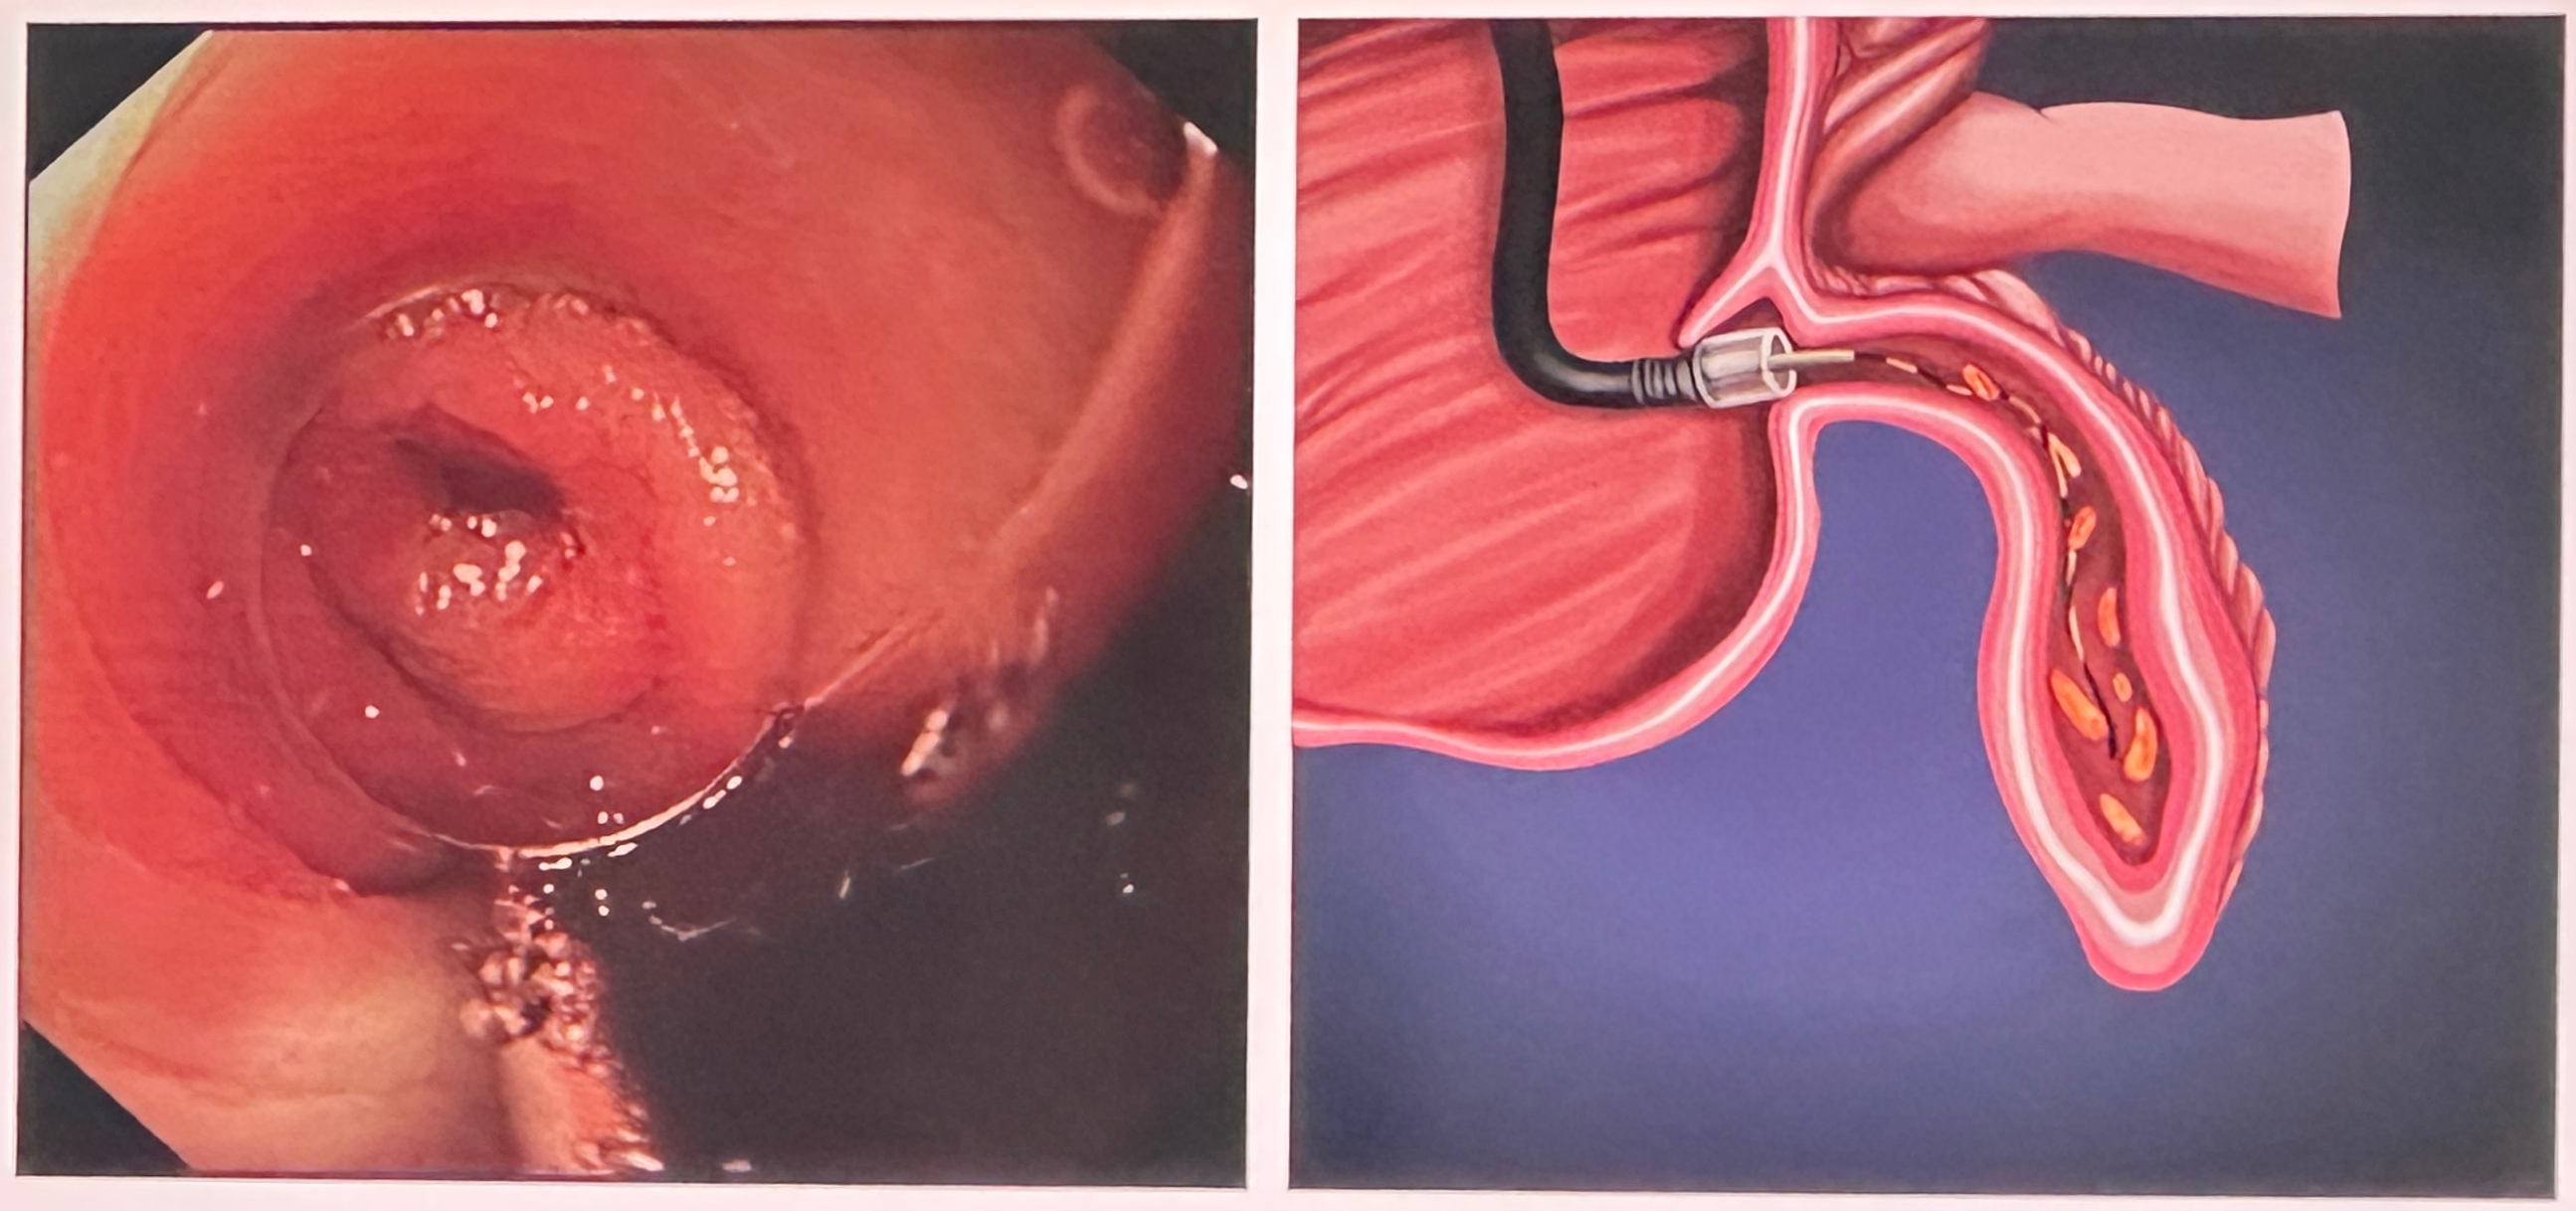

手术医生娴熟地将结肠镜经患者肛门送至回盲部,精准找到阑尾开口。在子镜辅助下,清晰地显示了阑尾腔内因粪石梗阻导致的肿胀和化脓,随后,利用球囊扩张阑尾开口,取出堵塞的粪石,并用生理盐水反复冲洗阑尾腔,脓液被引流干净,阑尾压力迅速缓解。整个过程,患者仅在镇静状态下进行,腹部无任何切口,术后清醒即可下床活动,疼痛感几乎消失。第二天就能正常进食,很快便顺利出院,回归正常工作和生活。

知识链接:什么是ERAT? ERAT(经内镜逆行性阑尾炎治疗术):是一种通过结肠镜,经肛门逆行到达阑尾开口,对其进行检查、引流、冲洗、取石等操作,从而治愈阑尾炎的超微创技术。 优势: 保留器官:不切除阑尾,维护肠道免疫功能的完整性,ERAT通过疏通而非切除,保留了阑尾的正常生理功能,更契合“精准医疗”的理念。 体表无痕:通过自然腔道进行操作,腹部无切口,完美满足患者对美观的需求,同时避免了切口感染、愈合不良等问题。 恢复迅速:术后疼痛轻微,无需长期卧床,可快速恢复饮食和活动,住院时间短,大幅减少对工作和生活的影响。 诊断精准:可直接观察阑尾开口,镜下直视明确诊断,安全性高,并发症少。 不过需要注意的是,ERAT并非适用于所有阑尾炎患者,目前主要适用于单纯性、未穿孔的急性阑尾炎或阑尾粪石导致的慢性阑尾炎,且阑尾开口可被内镜找到的患者。如果患者已出现阑尾穿孔、坏疽,或形成巨大腹腔脓肿,仍需及时采用传统手术或腹腔镜手术治疗。